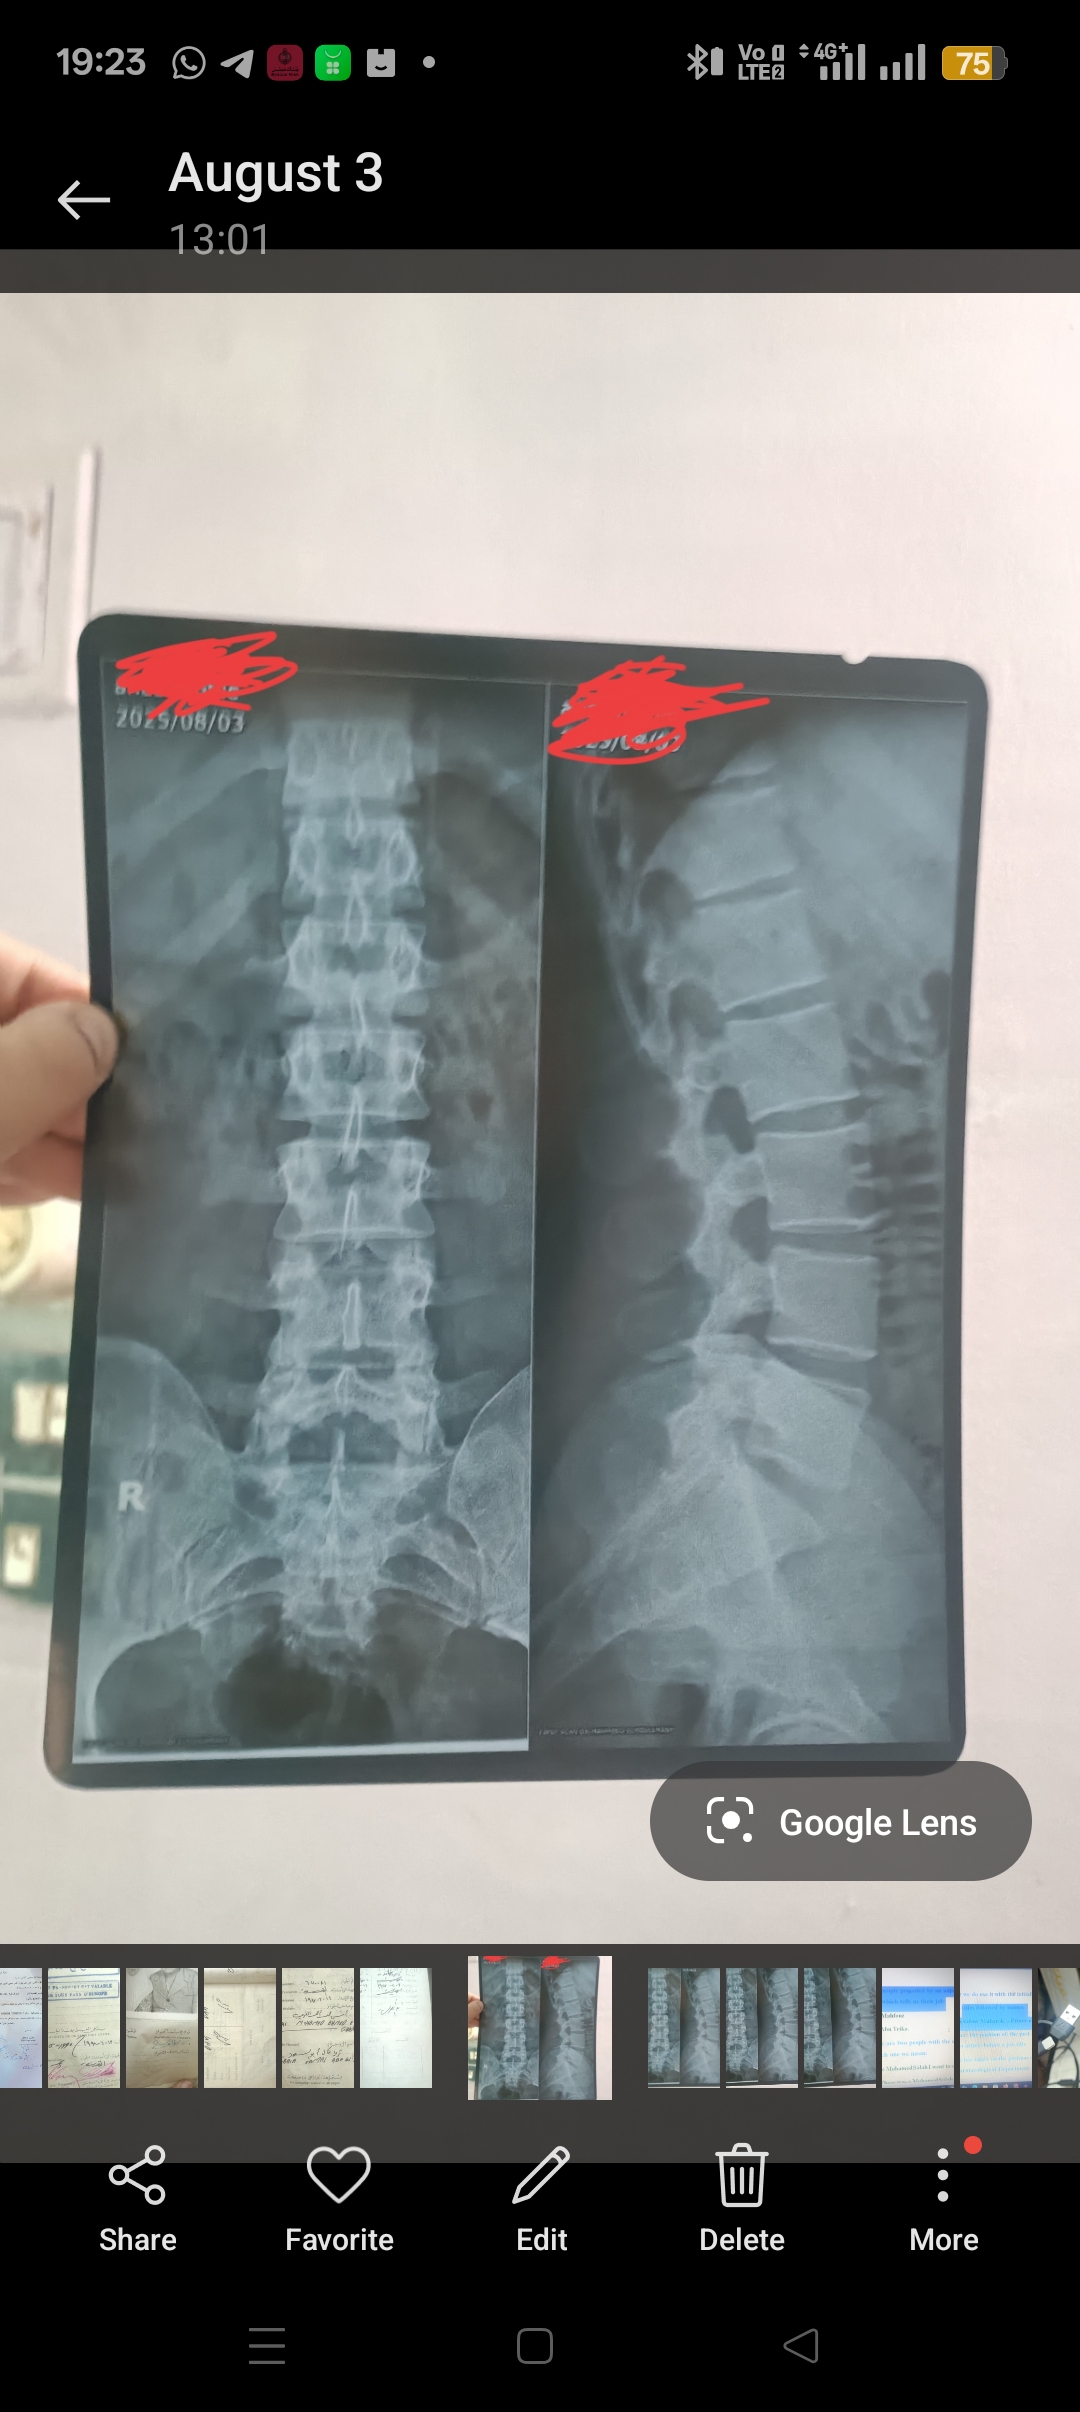

هل يوجد حل لإلتهاب هذه العضلة؟ quadratus lumborum إلتهاب مزمن وألم يزداد بالحركة والجلوس ويقل بالراحة والنوم وأشعة العمود الفقري سليمة (مكان الألم هو نفس مكان العضلة)

الملفات المرفقة:

1000096944 1000096876